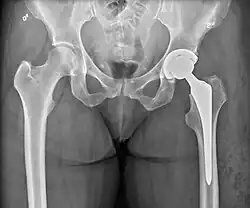

Hemiarthroplasty

.jpg)

Hemiarthroplasty is a surgical procedure that replaces one half of the joint with an artificial surface and leaves the other part unchanged. This class of procedure is most commonly performed on the hip after an intracapsular fracture of the femur neck (hip fracture). The procedure is performed by removing the head of the femur and replacing it with a metal or composite prosthesis. The most commonly used prosthesis designs are the Austin Moore and Thompson prostheses. A composite of metal and high-density polyethylene that forms two interphases (bipolar prosthesis) can be used. The monopolar prosthesis has not been shown to offer any advantage over bipolar designs. The procedure is recommended only for elderly/frail patients, due to their lower life expectancy and activity level. This is because over time the prosthesis tends to loosen or to erode the acetabulum.[101] Independently mobile older adults with hip fractures may benefit from a total hip replacement instead of hemiarthroplasty.[102]

Hip prosthesis for hemiarthroplasty. This example is bipolar, meaning that the head has two separate articulations. -

X-ray of the hips, with a right-sided hemiarthroplasty